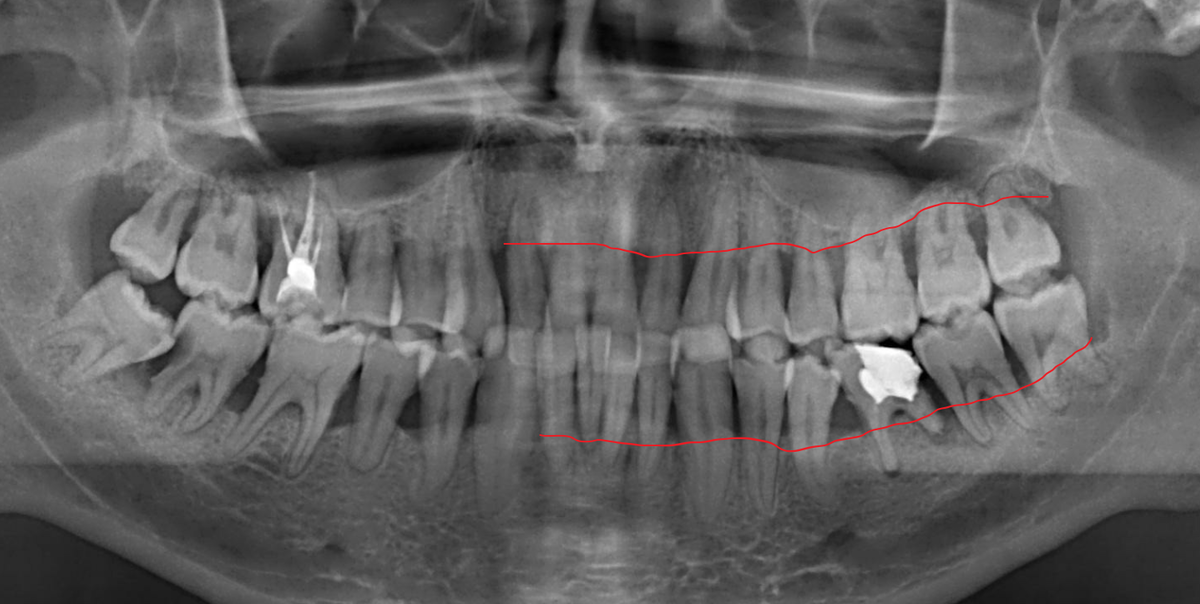

Пародонтит тяжёлой степени тяжести

Видите (красной линией отметила) насколько равномерно "ушла" кость? Процесс затронул все зубы. Этому человеку, увы, особенно не повезло.